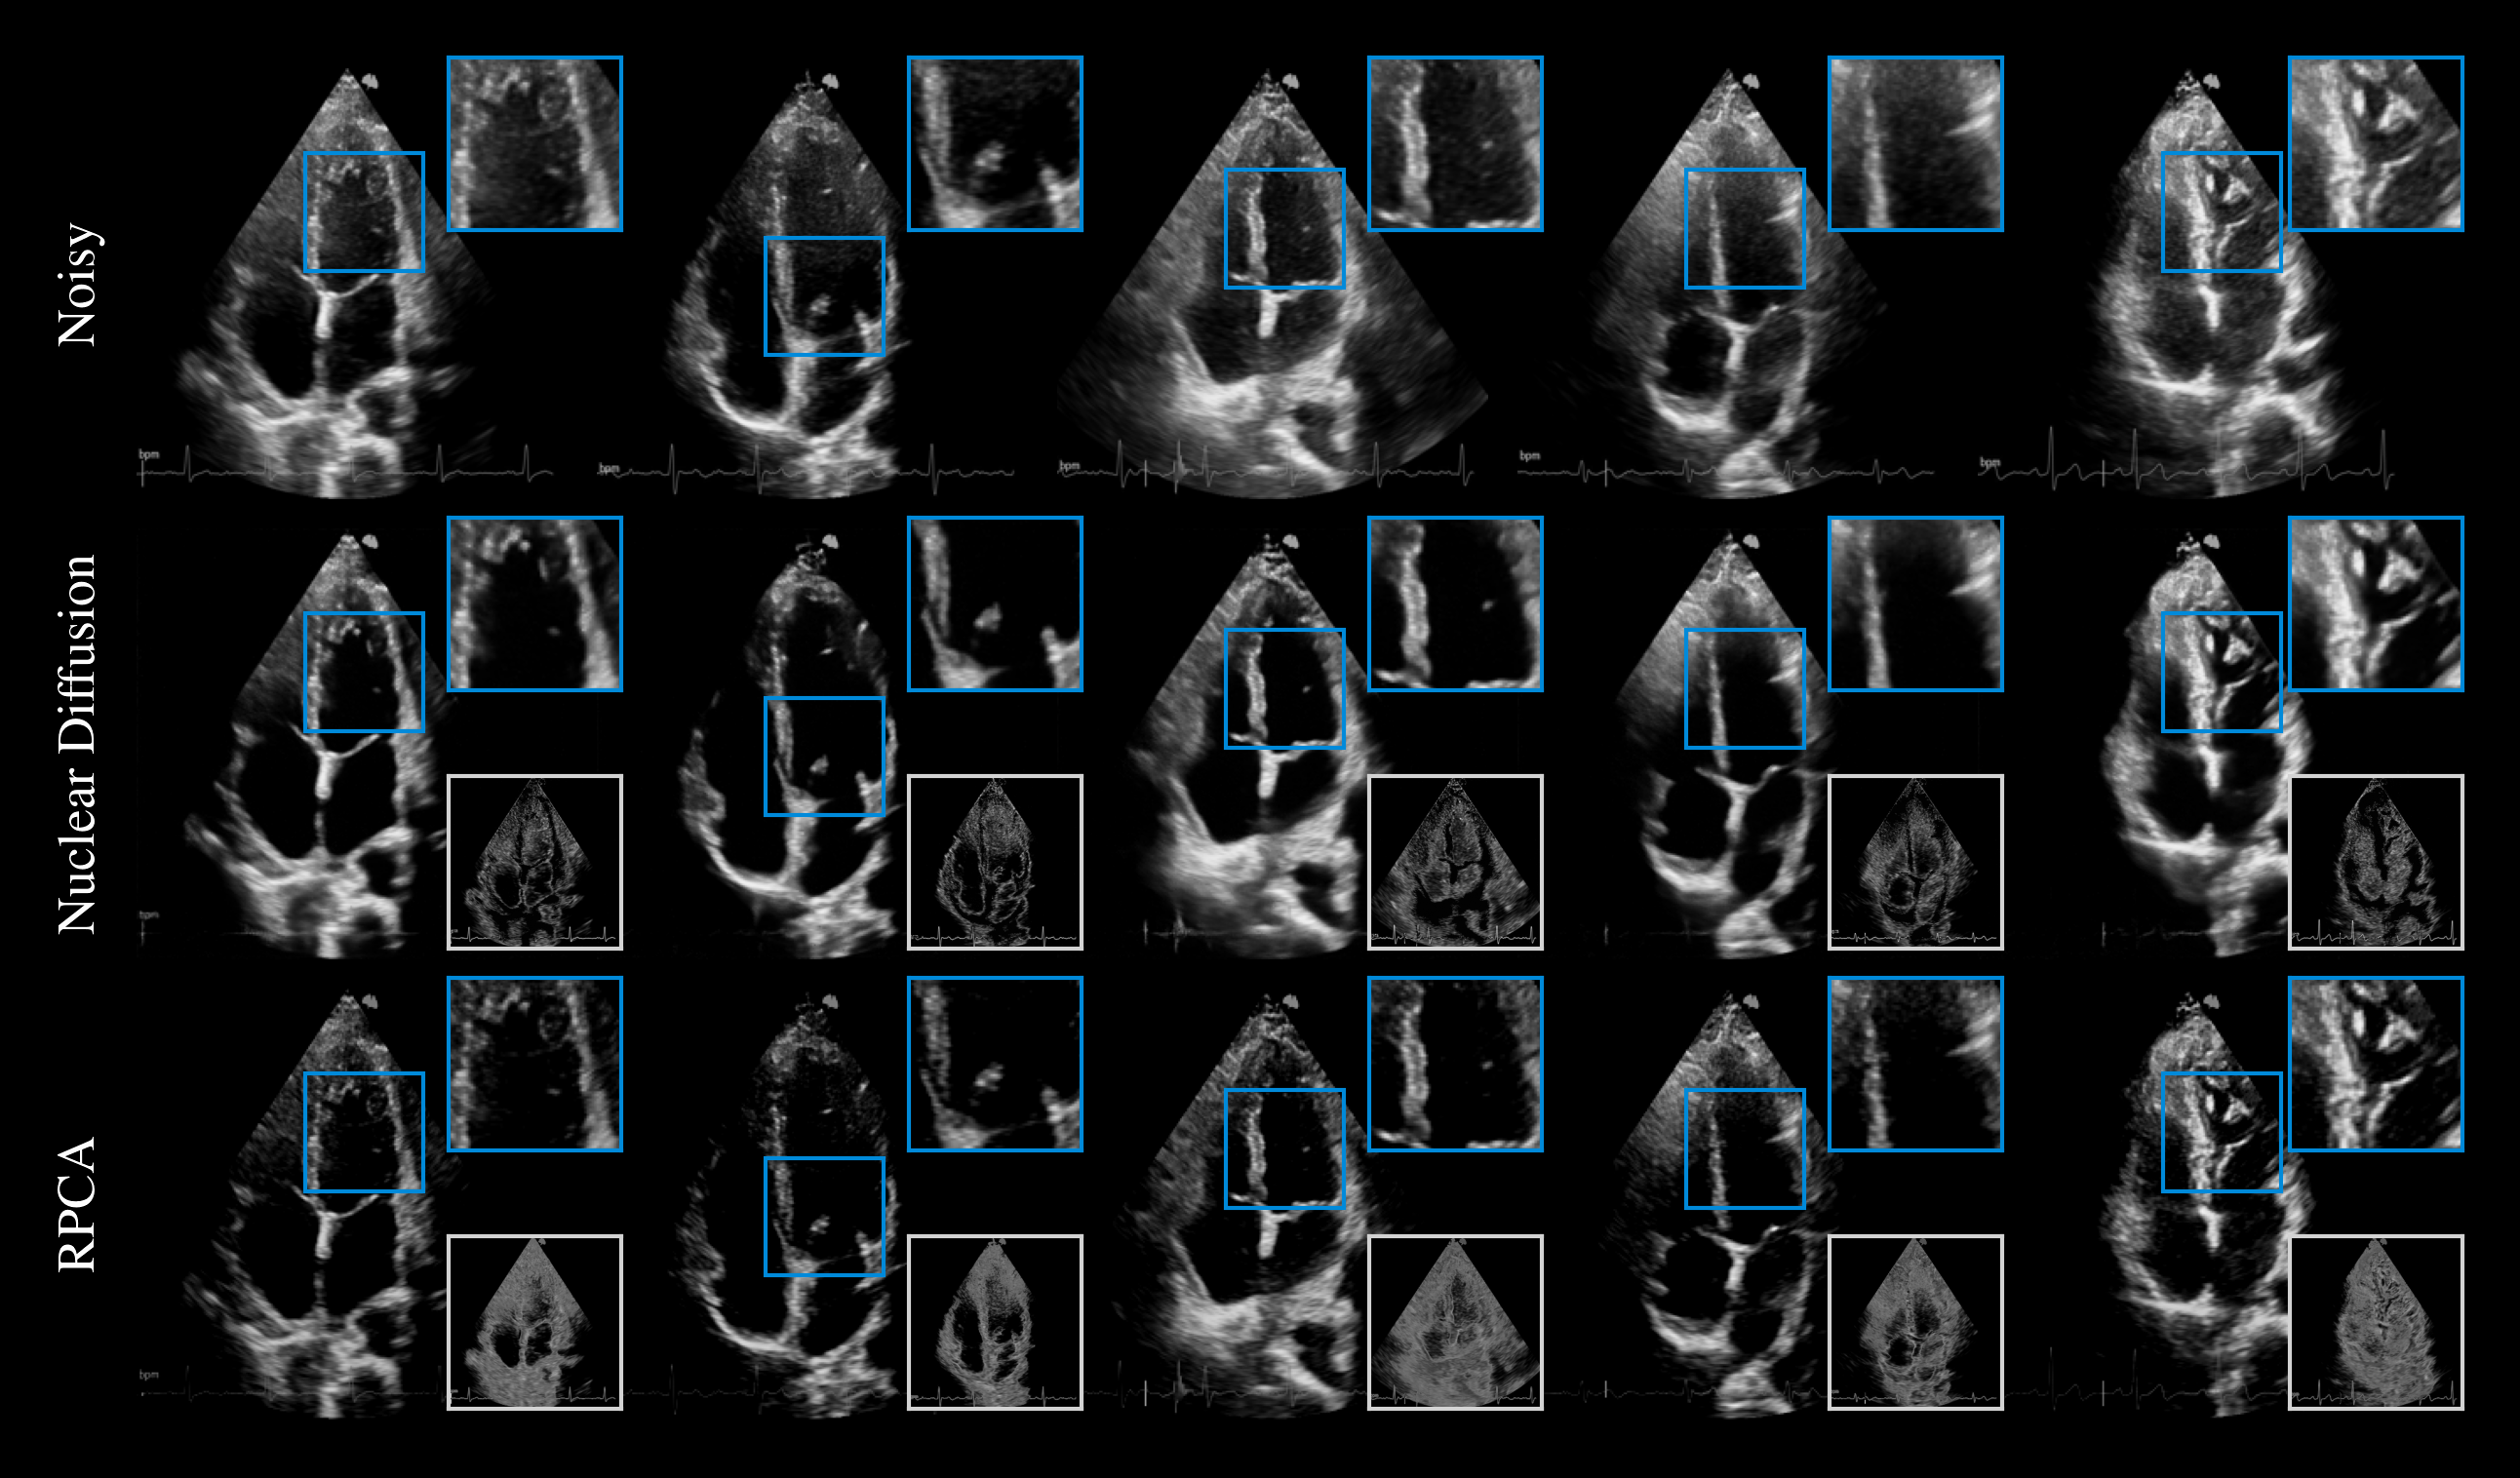

Comparison on the task of cardiac ultrasound dehazing. While both methods suppress haze (shown in bottom insets), RPCA tends to excessively attenuate tissue, resulting in sparse structures, whereas Nuclear Diffusion better preserves details.